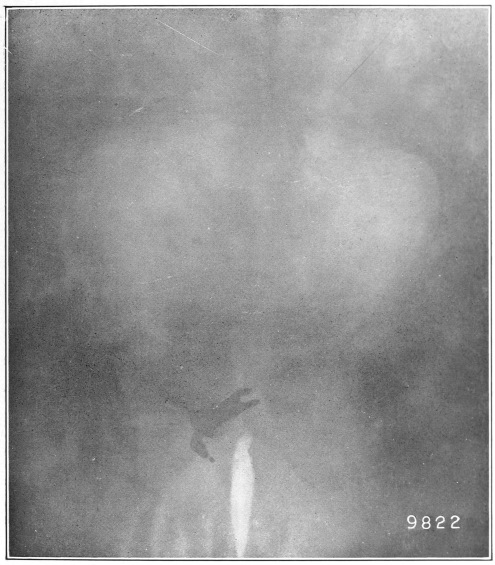

Nine Radiograph Illustrations Showing Mucus Channels and Cavities200